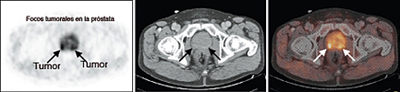

En los pacientes con enfermedad de bajo riesgo no es necesario, en general, la realización de TAC o RMN (resonancia magnética endorectal) que sí lo son en los pacientes del grupo de riesgo intermedio y elevado.

El estudio de los huesos mediante gammagrafía ósea debe ser efectuado si hay sospecha de lesiones óseas y/o el PSA es superior a 10 ng/ml. En ocasiones se realiza un PET-TC con colina para evaluar la presencia de metástasis.

RMN endorectal. Es una técnica de imagen que utiliza ondas magnéticas en lugar de rayos-X. La energía de las ondas magnéticas es absorbida por el organismo y después liberada dando las imágenes más detalladas que hoy en día podemos obtener de la próstata. La calidad de las imágenes, asociada en ocasiones con técnicas de espectroscopia o de inyección de contraste paramagnético es tan elevada que permite observar la zona de HBP y, si hay tumor, diferenciar entre un tumor en estadio T2 y un T3 con una especificidad del 95%. También permite detectar la presencia de ganglios linfáticos aumentados de tamaño, en la zona pelviana y es de gran ayuda para planificar las biopsias pues nos indica que áreas son sospechosas de albergar células cancerosas.